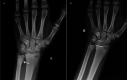

Isolated distal ulna epiphyseal plate injuries are very rare and are often associated with early epiphyseal plate arrest. A 13-year-old boy sustained an isolated minimally displaced Salter-Harris type II fracture of the left distal ulna following a fall from a bicycle. The fracture was reduced, and a long arm plaster cast was applied for four weeks. At the six-month follow-up, the patient presented with a painless, full range of movement of the left wrist, but on radiological examination, a mild shortening of the ulna was detected. We plan to regularly evaluate this patient until distal epiphyseal plate closure and surgically intervene if necessary. To our knowledge, this is the third Salter-Harris type II distal ulnar fracture ever reported, and the second treated nonoperatively. It was shown to be associated with a mild growth disturbance. Although Salter-Harris type II injuries are considered benign, surgeons should closely evaluate this rare type II isolated distal ulnar fracture and inform parents regarding possible future complications, which range from clinically insignificant cosmetic deformity to severe instability of the distal radioulnar joint, depending on the degree of shortening.